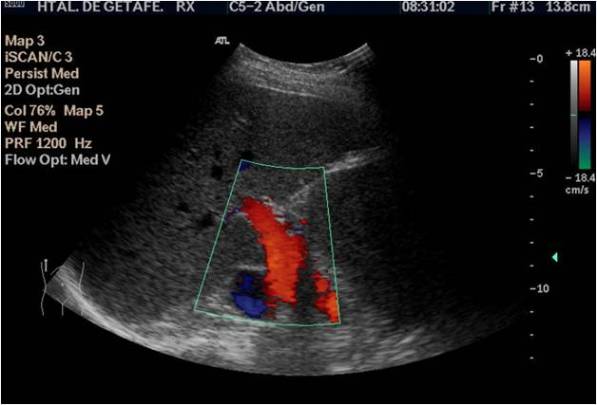

La ecografía mostró una tumoración en la región del cordón espermático derecho de unos 4cms, siendo una lesión sólida,hipoecogénica, muy bien delimitada y moderadamente vascularizada en el Doppler color.

Después aplicamos el doppler, tanto el color como el modo angio donde observamos la vascularización del tumor, ojo a la escala que usemos, tiene que estar adaptada a la vascularización de la ecoestructura que estemos estudiando para ver la correctamente, de nada me sirve poner el doppler si la escala no está bien ajustada ,es decir, demasiado alta o baja, de ese modo, las lecturas de flujos lentos o rápidos no serán estudiadas por mala técnica.

Si observas en el margen superior izquierdo de la imagen 3 y la imagen 4 vas a ver que la escala es baja (3,8 cm/sg), por tanto el flujo de la lesión sabemos que es baja. Si nosotros usamos una escala muy alta, no podríamos ver las imágenes que estás viendo, y como en esta imagen, en todas las imágenes de neoformaciones a las que te enfrentes en tu día a día.